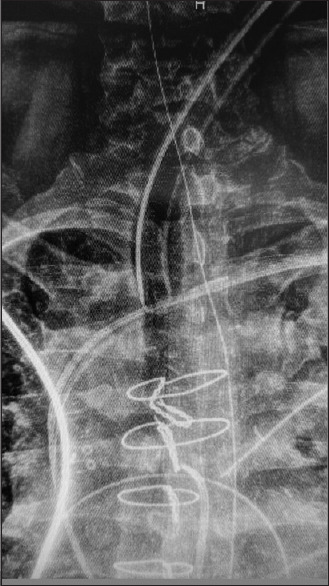

摘要:全喉切除术后气道给围手术期麻醉管理带来了挑战。虽然支气管内插管是一种常见的并发症,但低位造口可能会增加这种风险。此外,造口靠近胸骨正中切口也增加了手术和气道管理的复杂性。本报告重点介绍了一例低位造口患者进行支气管内插管的病例,该患者前来接受冠状动脉旁路移植手术。由于造口位于胸骨上缘,因此需要在术中进行创新,以防止气管内插管,同时保持在手术视野之外。这种创新在紧急手术情况下可能很有用。

Abstract: The post-total laryngectomy airway poses perioperative challenges to anesthesia management. While endobronchial intubation is a cited complication, a low-lying stoma may increase this risk. Furthermore, the stoma's proximity to a median sternotomy increases surgical and airway management complexity. This report highlights a case of endobronchial intubation in a patient with a low-lying stoma who presented for coronary artery bypass graft. With a stoma at the upper border of the sternum, intraoperative innovation was required to prevent endobronchial intubation while remaining out of the surgical field. This innovation may be useful in urgent surgical situations.